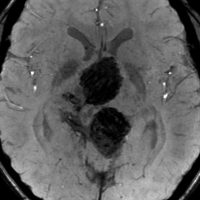

9歳男児の松果体奇形腫です。生検術と第3脳室開窓術を受けましたが,摘出術のリスクが高すぎるということで化学療法を6コース。2年間経過観察されましたが,腫瘍が増大しました。私のところへ来た時には,前後径73mmありました。

左からT2, swan, T1です。これが 類皮のう胞 dermoid cyst ということがわかります。類皮のう胞単独,あるいは成熟奇形腫の大部分としての類表皮のう胞は,かなり頻度の高いものです。松果体腫瘍で奇形腫を疑ったらまず,類皮のう胞の混在を疑います。それがあれば,かなりの確率で成熟奇形腫 mature teratomaです。

類皮のう胞は内部がほとんど皮脂,ケラチン,汗,毛髪なので,簡単に砕けるし,掻き出し吸い取ることができます。松果体成熟奇形腫の中では最も戦いやすい相手と言えるでしょう。再発しないようにするには,周囲ののう胞壁(真の腫瘍細胞)を完全摘出するしかありません。放射線も化学療法も何も効かないし,のこせば必ず再発します。

右迂回槽にちょっとdebrisは残っていますが完全摘出できました。病理は他の成分を少し混じる成熟奇形腫です。術後3年間再発はありませんし,学校へ通って体育もできています。

この手術はもちろん簡単ではありません,でもほとんどが類皮のう胞であるということがわかったので踏み込めたのです。